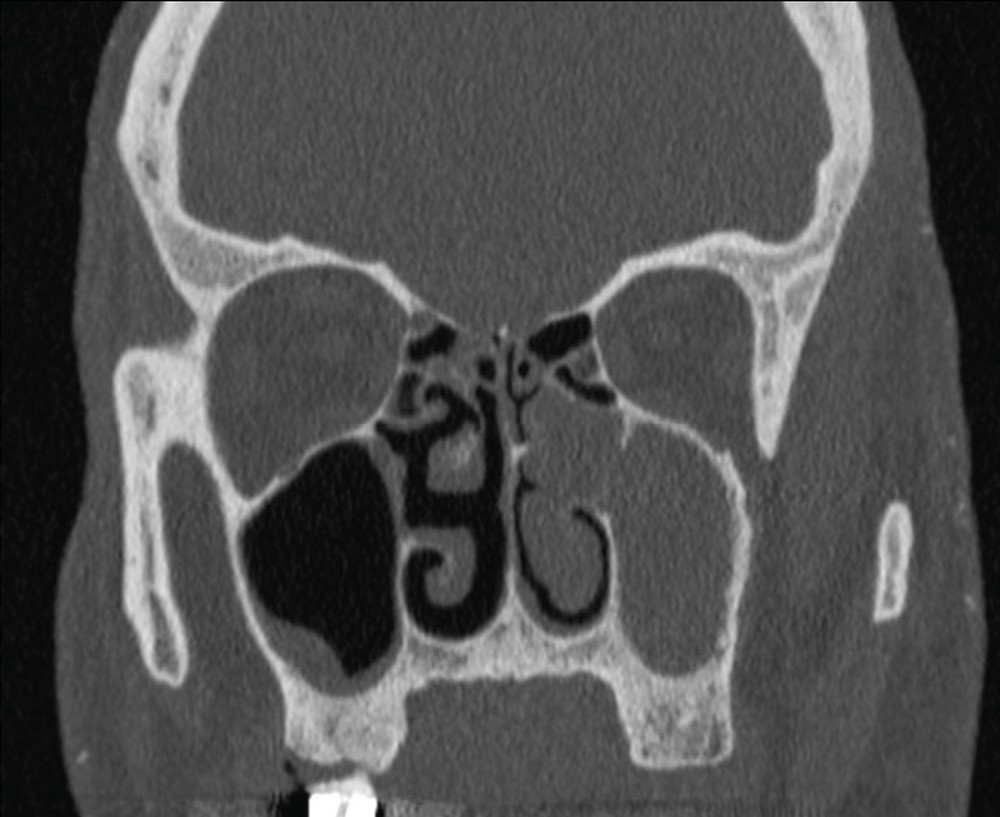

La tomodensitométrie des sinus retrouve un comblement complet unilatéral du sinus maxillaire gauche et des cellules ethmoïdales antérieures homolatérales, sans image de densité calcique intrasinusienne et sans lyse osseuse des parois (fig. 1). L’IRM montre un épaississement tissulaire de 23 mm de grand axe en regard du méat moyen gauche, avec un aspect de signal T2 hétérogène (fig. 2) et prenant le contraste en masse (fig. 3). Le comblement maxillaire gauche associé à un épaississement muqueux en cadre rehaussé correspond à une rétention en hypersignal en diffusion (fig. 4), avec diminution du coefficient apparent de diffusion (moyenne à 433 mm2/s) en faveur d’une pyocèle (fig. 5).